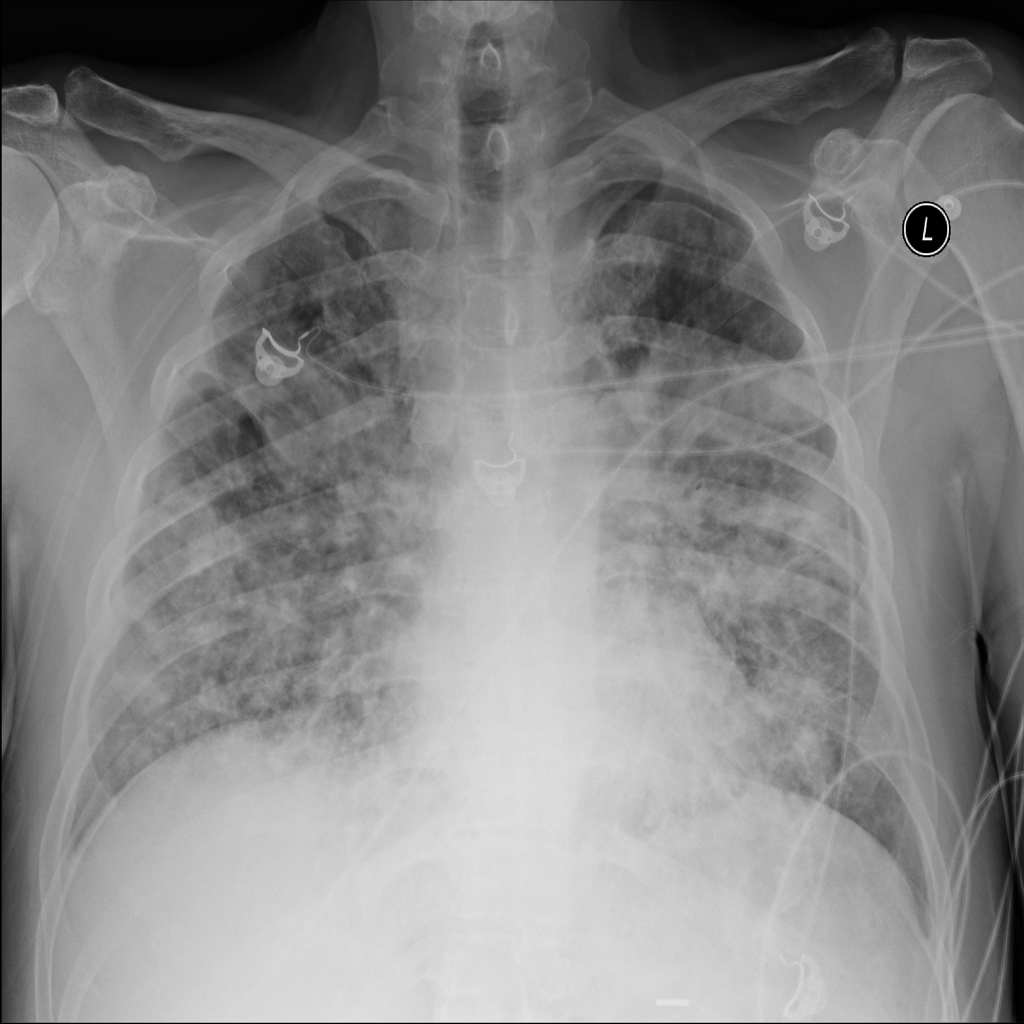

PAT-4639 · IMG-020Pneumothorax

PAT-4639 · IMG-020

PA